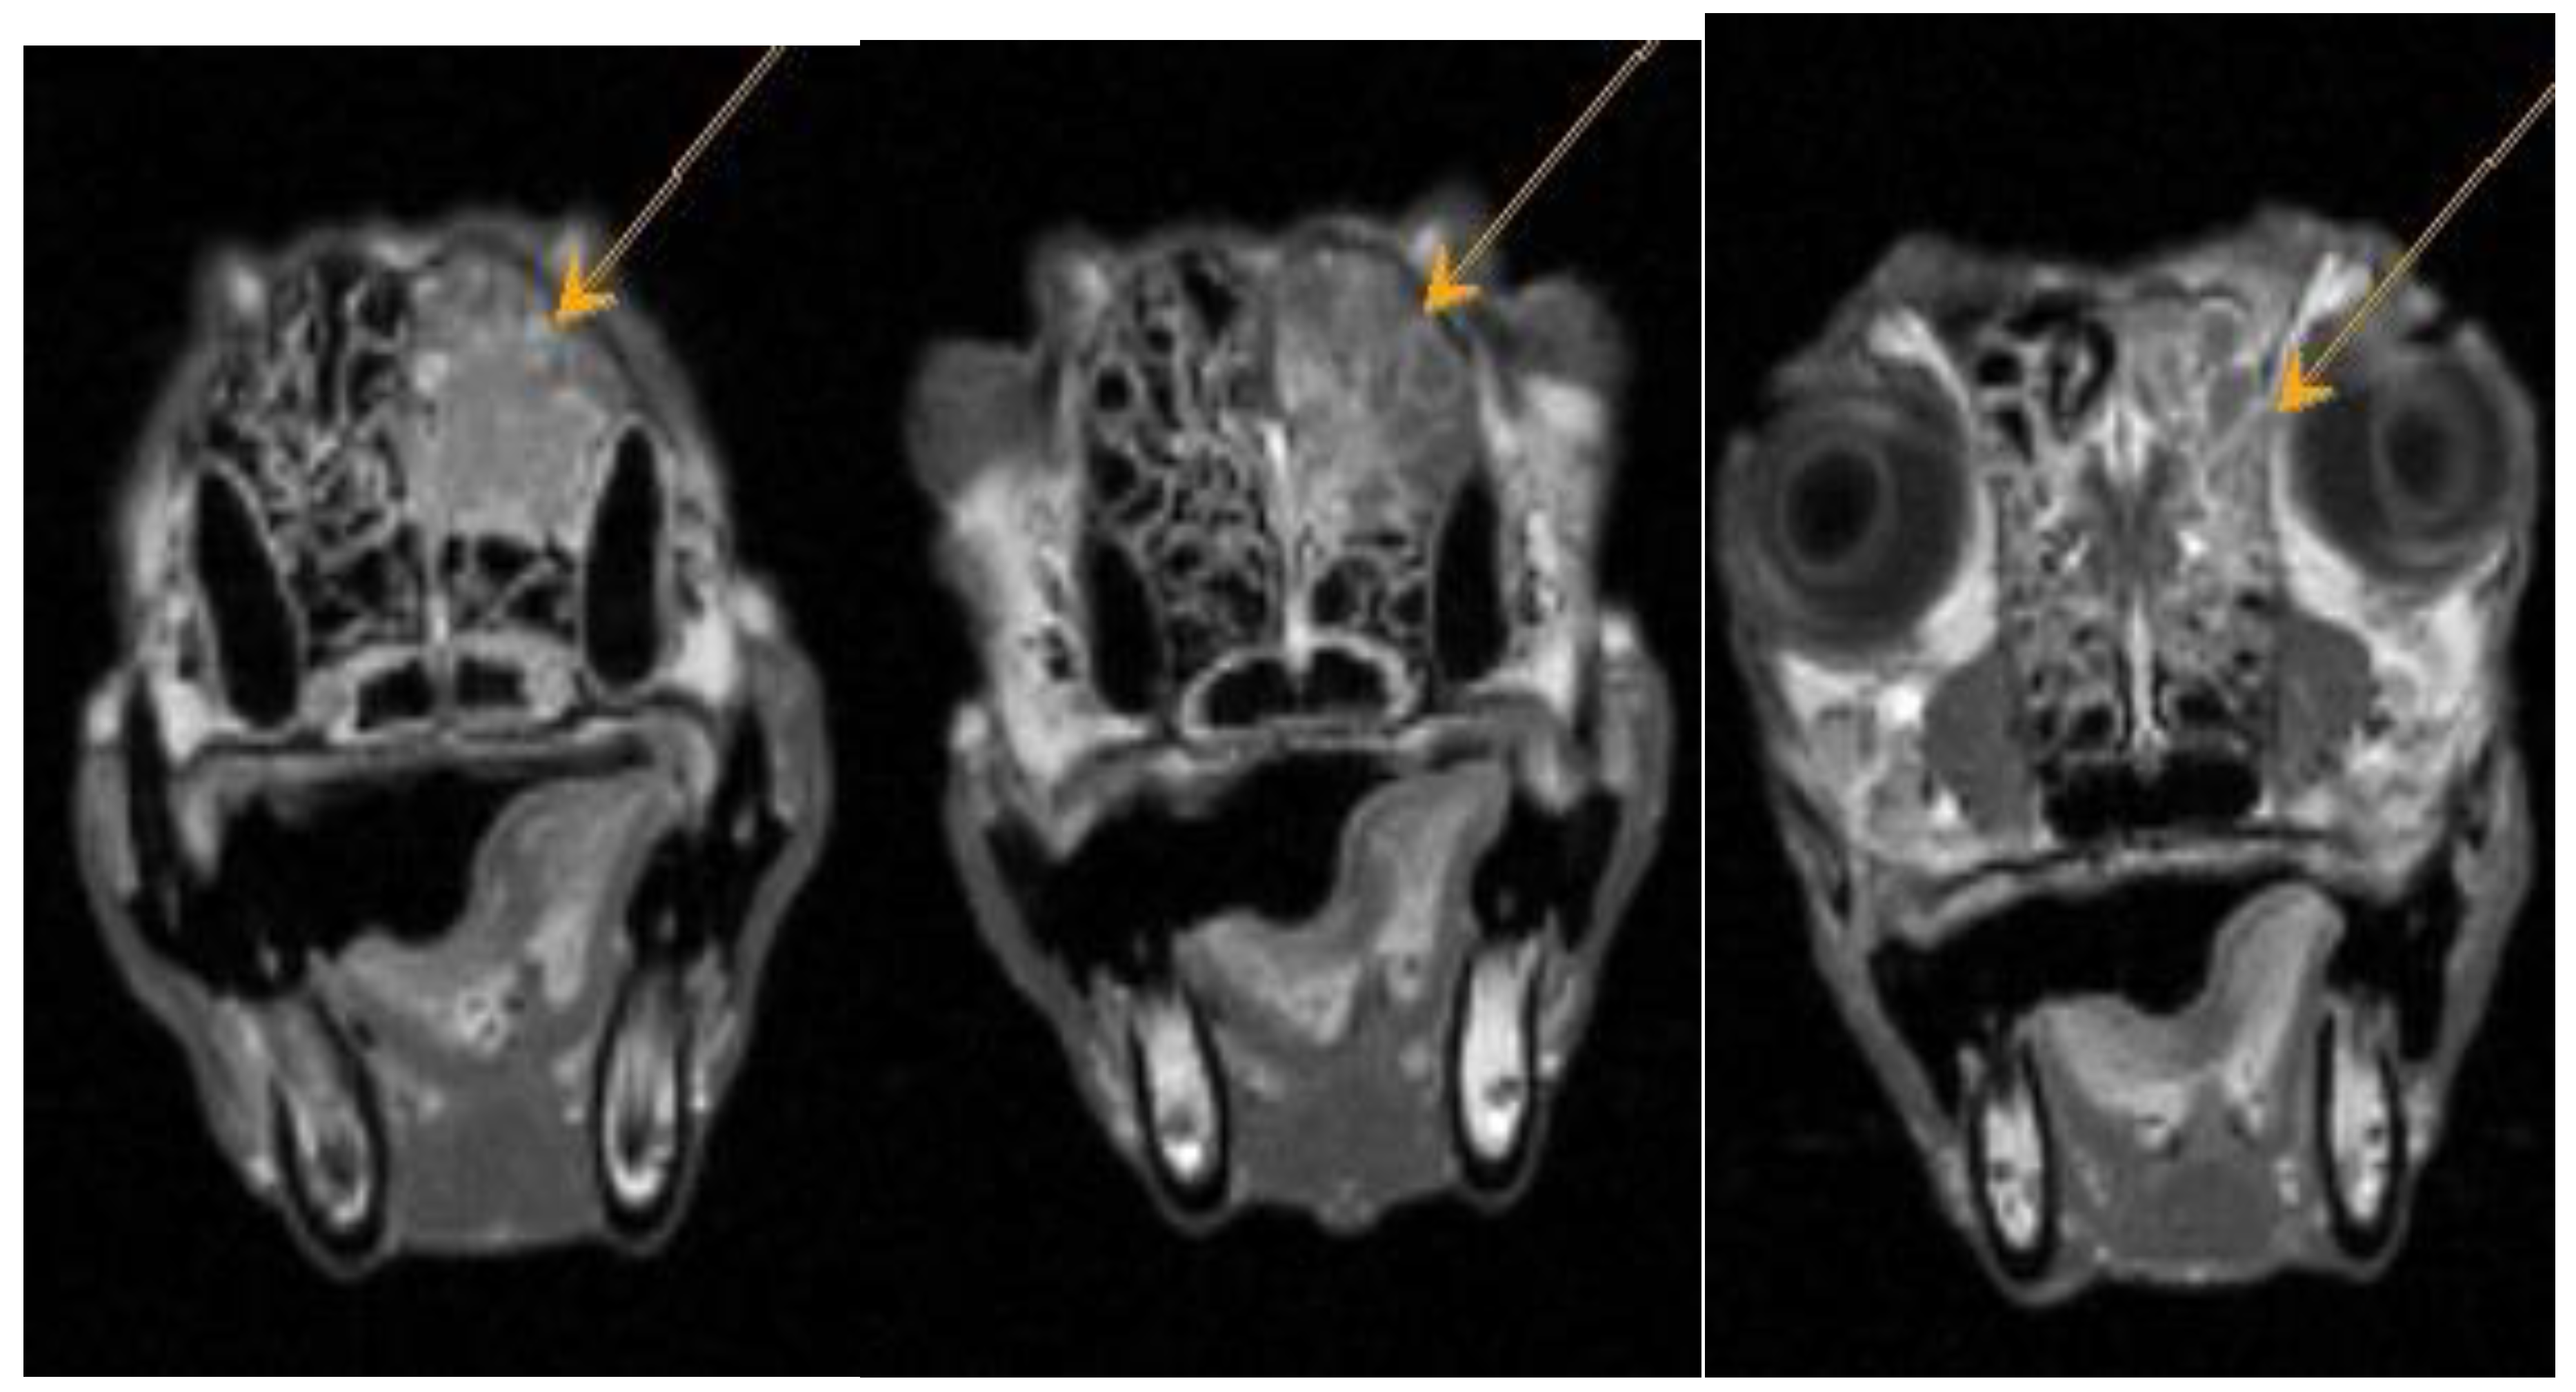

Figure A4. Dachshund dog, 13 years old, 9 kg. T1-VI mode axial plane. Heterogeneous weakly hyperintense signal from the nasal cavity - neoplasm.

Figure A5. Dachshund dog, 13 years old, 9 kg. T1-VI mode axial plane, after administration of a contrast agent (CA). Diffuse focal accumulation of CA in the nasal cavity is a neoplasm.